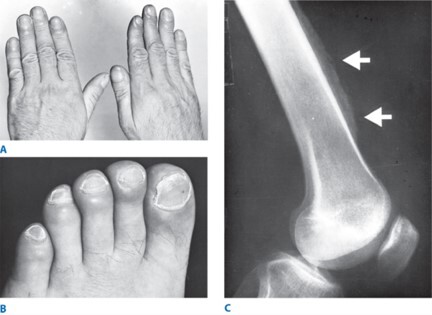

clubbing

-not exclusive to lung cancer

SCLC

-Central Necrosis

-toes, bones, and perio-osteo overgrowth -> hypertrophic pulmonary osteoarthropathy